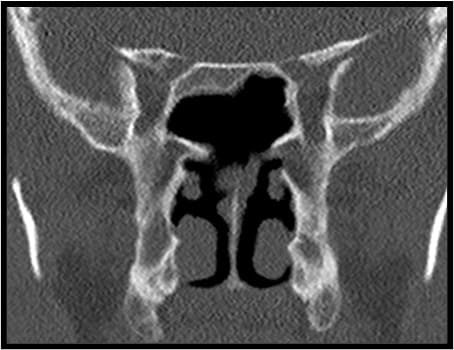

Figure 3: (A) Coronal cadaver view of the sphenoid sinuses. (B) Axial CT-scan demonstrating an oblique paramedian intersinus septum and a bony partition in the left sphenoid sinus.